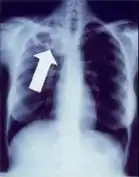

Chest X-ray

Tuberculosis creates cavities visible in x-rays like this one in the patient's right upper lobe.

2. Any cavitary lesion - Lucency (darkened area) within the lung parenchyma, with or without irregular margins that might be surrounded by an area of airspace consolidation or infiltrates, or by nodular or fibrotic (reticular) densities, or both. The walls surrounding the lucent area can be thick or thin. Calcification can exist around a cavity.